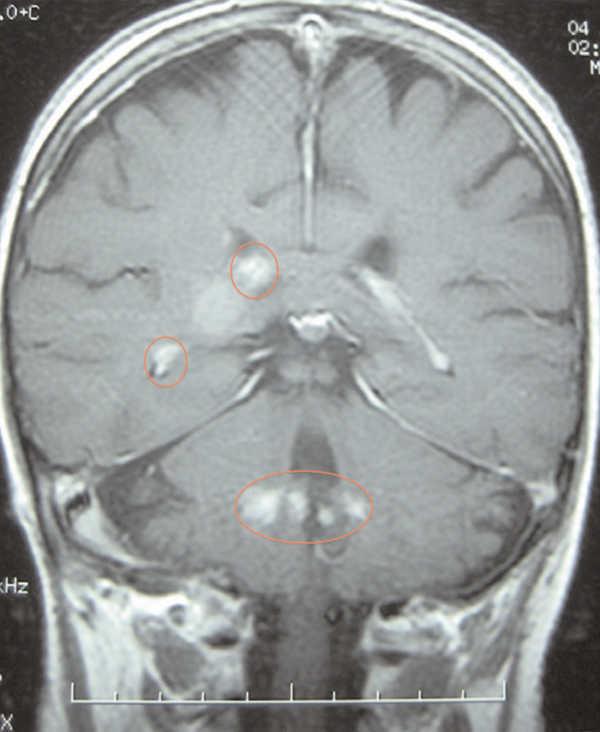

A 66-year-old female, with chronic kidney failure secondary to hepatorenal polycystosis, which received a deceased-donor kidney transplant and treatment with basiliximab, steroids, mycophenolate mofetil and tacrolimus. She suffered a type IIb cortical-resistant acute rejection and needed treatment with OKT3. After four months she was admitted for fever, general discomfort and intense asthenia. She was diagnosed with suspected pulmonary tuberculosis by chest computed tomography (CT) and fibrobronchoscopy, confirmed by Ziehl-Neelsen staining and Löwenstein culture. She was prescribed treatment with rifampicin, isoniazid and pyrazinamide for two months, followed by rifampicin and isoniazid for four months. After 15 days she was readmitted for confusion, occipital cephalgia and visual alterations. In a brain resonance, multiple hypertensive nodules were seen in T2, with nodular focal contrast in the right frontal, subcortical, suprasylvian, right occipital areas and in cerebellar peduncles, indicative of granulomatous infiltration secondary to tuberculosis (Figure 1). Treatment with isoniazid and rifampicin was extended to nine months and the patient recovered.

Figure 1. Cerebral tuberculoma